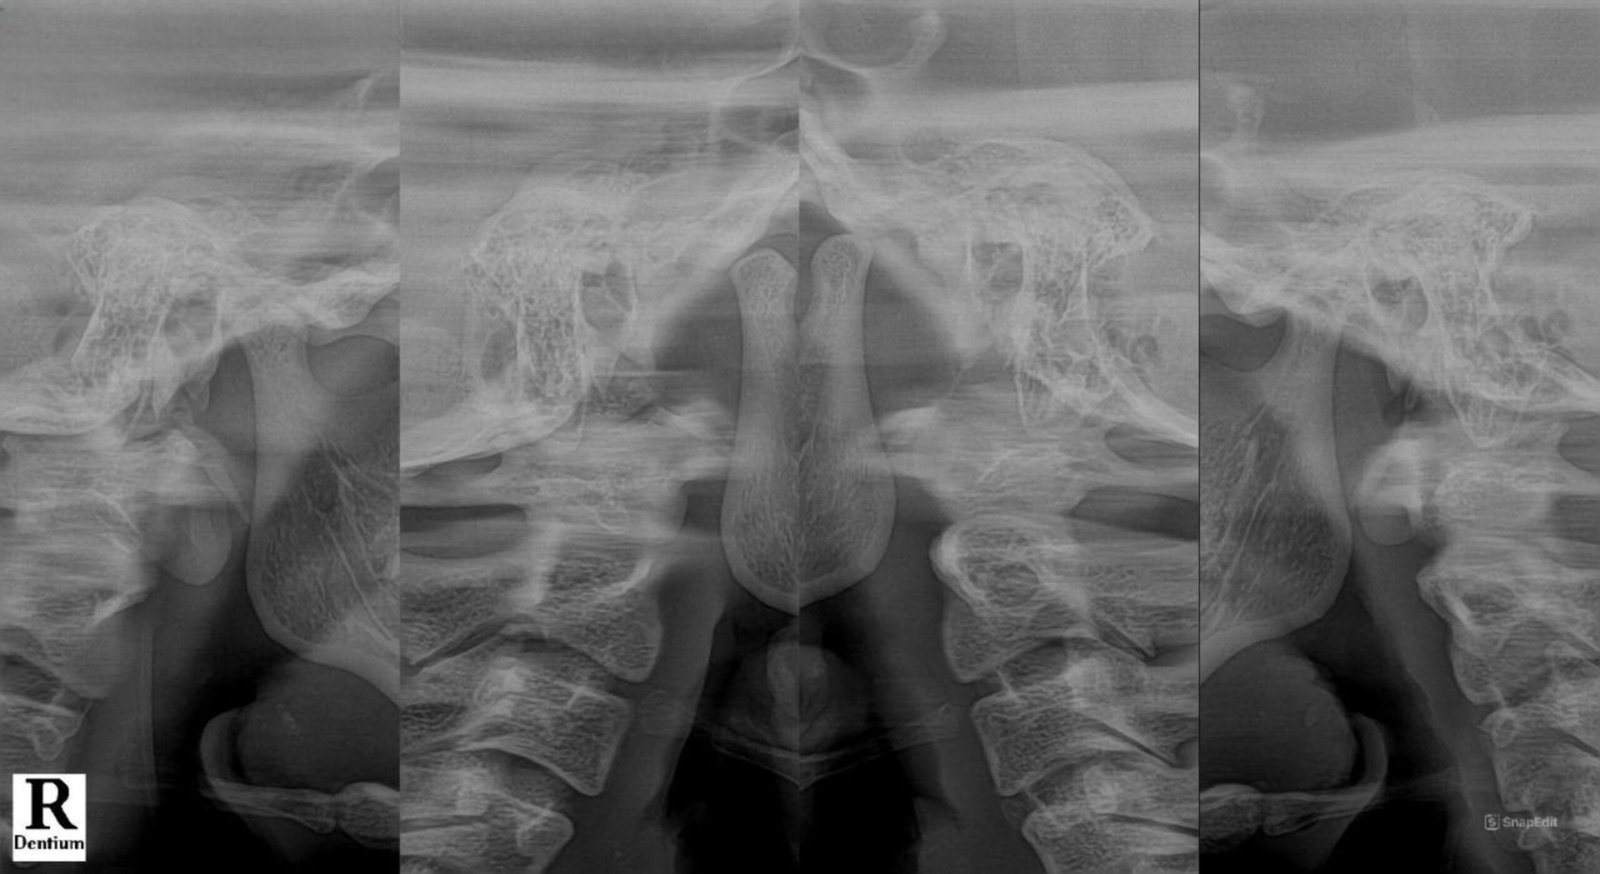

TMJ (PANORAMIC VIEW)

Rontgen TMJ (Panoramic View) ini menunjukkan pemotretan persendian antara tulang mandibula dan tulang temporal pada cranium.